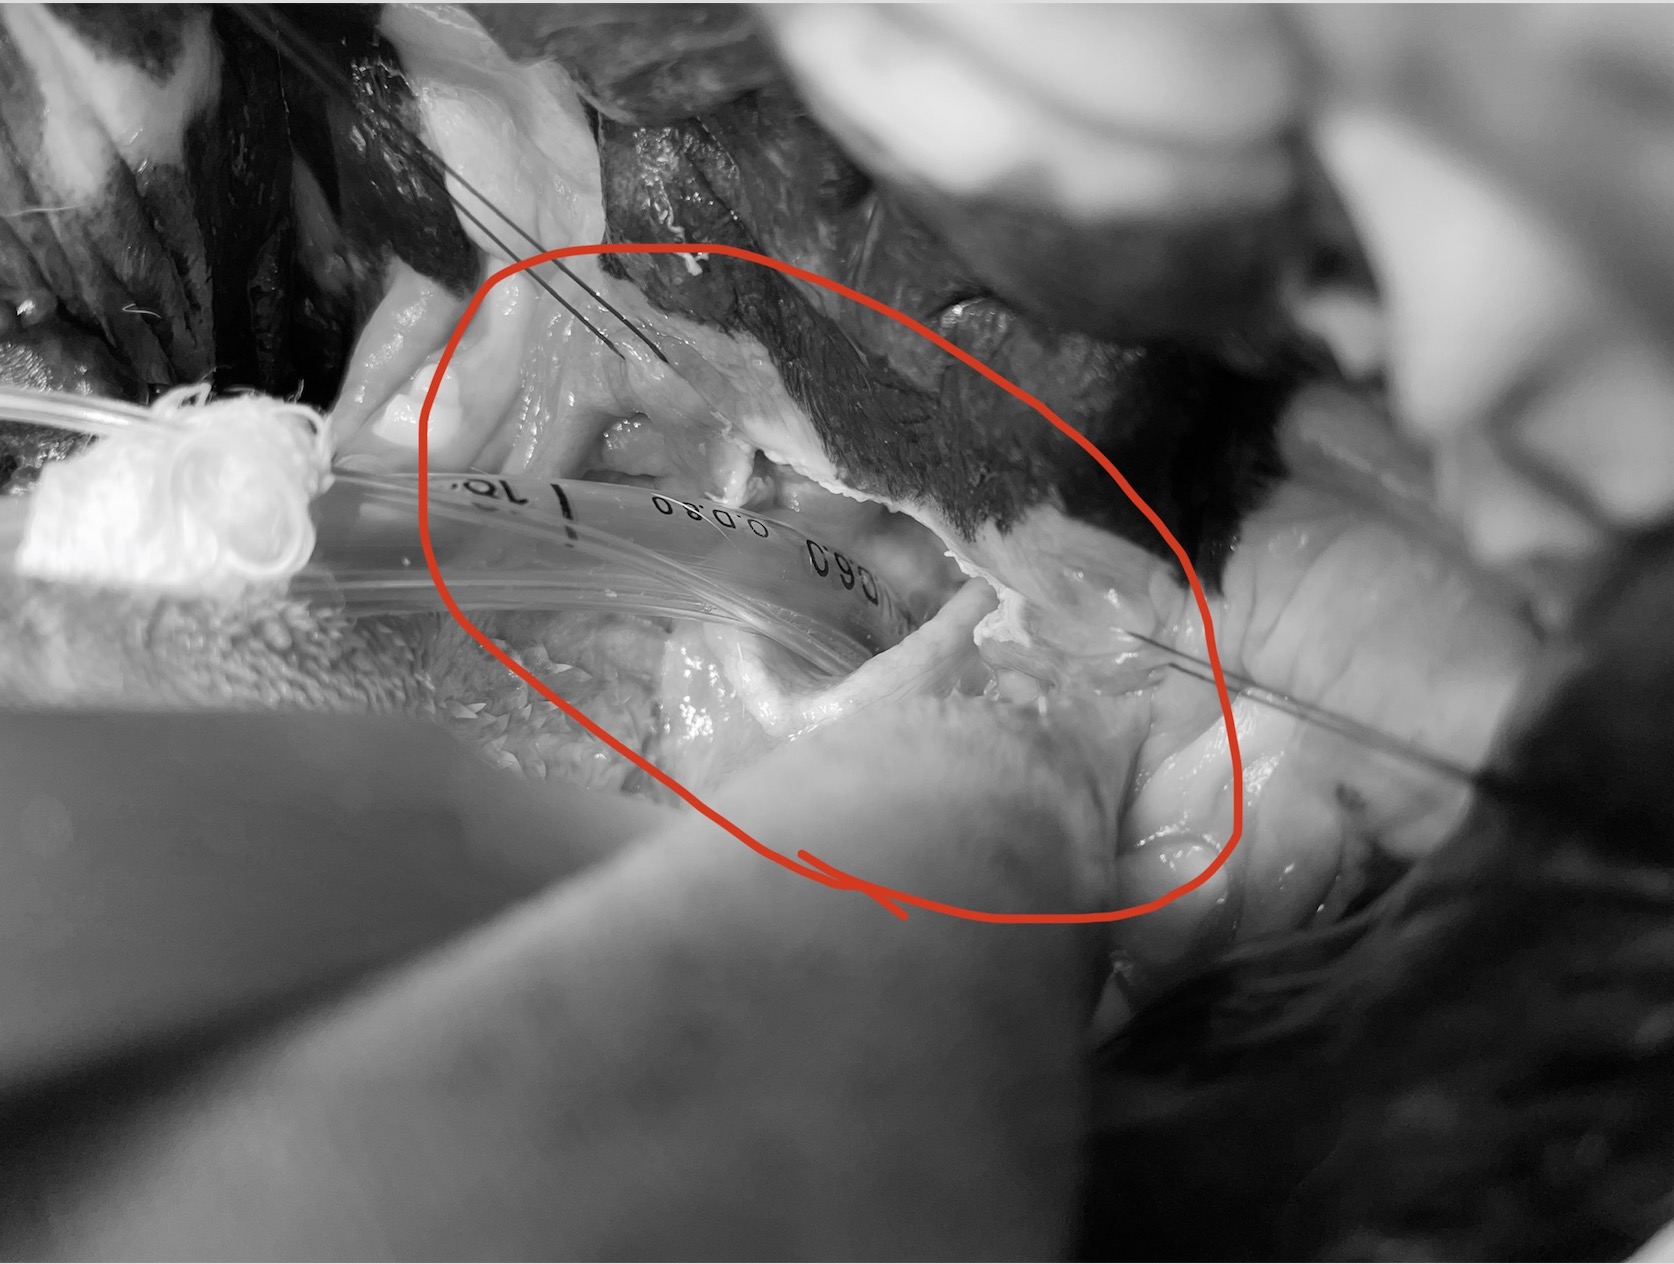

上の写真は気管挿管時に軟口蓋を牽引した画像です。

軟口蓋は非常に分厚く、気管の入り口に覆いかぶさるように存在していました。

手術では軟口蓋の辺縁を切除しました。